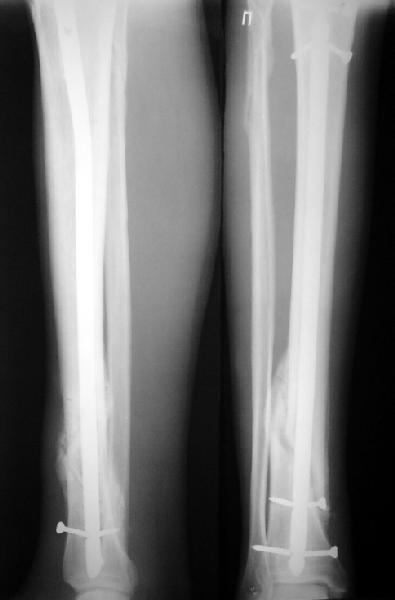

На мой взгляд, на снимках, приведённых Вами - неправильно сростающийся перелом дистальной трети большеберцовой кости, состояние после остеосинтеза интрамедуллярным гвоздём.

Как Вы пишите снимок под номером 1 - менсяц после операции, под номером 2- два месяца после операции.

I think that the X-Rays show S/P IMN of Spiral # of the Distal Tibia consoles in misalignment.

You wrote that a picture number 1 - f month after the surgery, and number 2-two months after the surgery.

You have not sent a postoperative X-Rays; so it's impossible to discuss about the condition of a reduction after operation.

Let to express concerning technique of operation my opinion... Insertion of a screw to medial side of a nail in distal fragment would help you to reduction and to keep this fracture in anatomic position has prevented varus deformity and displacement on width. By the way, if it is possible send a postoperative picture.